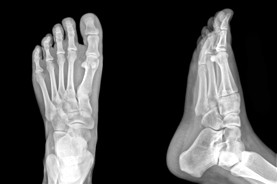

Edmonton Foot Doctor & Foot Physical Therapist

The Foot Institute is an association of Edmonton Doctors specializing in the medical treatment of the foot and ankle, and is one of the largest groups of foot specialists in Alberta.

The Edmonton Foot Institute is dedicated to the medical and surgical treatment of the foot. Our mandate is to provide the best possible medical, surgical and preventative treatment available for our patients. We do this by providing well-trained Doctors who are committed to treat and prevent all types of foot pain, biomechanical disorders, as well as all other problems relating to the feet.

At the Edmonton Foot Institute, our Doctors are trained to specifically treat problems associated with your feet or ankles. Below are several of the most common problems that we see on a day to day basis: